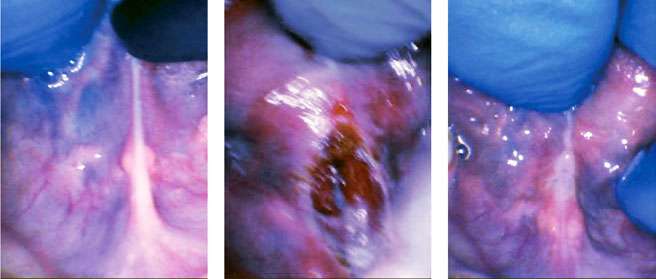

A nine-year-old autistic male patient who had trouble with speech, feeding, sleep, and reflux was presented by his mother for evaluation. His symptoms included frustration with communication, speech delay until age 5, poor speech intelligibility, chronic reflux since infancy, poor weight lifelong (4th percentile), and anterior loss of milk during bottle-feeding as a baby. Solid feeding had always been a challenge, and he was a “very slow eater.” He packed food in his cheeks “like a chipmunk”, choked and gagged on food, and spit food out frequently. His sleep quality and quantity were both poor according to his family. He had difficulty going to sleep, awakened easily and often, slept in strange positions, moved and kicked at night, ground his teeth, breathed orally at night, and snored often. His tongue-tie was a posterior tongue-tie and was therefore not recognized by his healthcare providers. It was not deemed to be a likely contributor to any of his issues previously (which is common in children with autism).

After a full history was obtained and all related symptoms, risks, and benefits of the procedure were discussed with his parents, they chose to have him undergo a lingual frenectomy. The instrument utilized was the 10,600 nm CO2 laser (LS-1005 LightScalpel, Bothell WA). The area was anesthetized with a compounded topical anesthetic, but neither nitrous oxide, oral sedation, general anesthesia, nor injected local anesthetic were used. A mouth prop was used, as well as two assistants to stabilize the patient, who was initially combative, but with the CO2 laser, the procedure was quick, and he calmed down even during the procedure itself. After 10 seconds of lasing at 3 W pulsed (Non-SuperPulse), 29 Hz, 72.5% duty (2.1 W avg), the tissue was vaporized with no bleeding or stitches, and minimal discomfort to the patient. The patient was instructed to perform oral exercises at home for three weeks postoperatively and the parents were shown how to do wound lifts if he would allow them. Two weeks later, the patient returned for a visit, and the mother reported that his “sleeping and eating improvement [had] been unreal.” It was easier for him to communicate, he was less frustrated when eating, his appetite had improved, he was swallowing more easily, he was finishing more of his meals, he was spitting food out less often, he was not gagging or choking on food at all, and he had less reflux. His sleep was also significantly improved. He fell asleep more easily and awakened less than before the frenectomy He moved and contorted his body less during the night. He snored less, stopped mouth breathing and quit grinding his teeth.